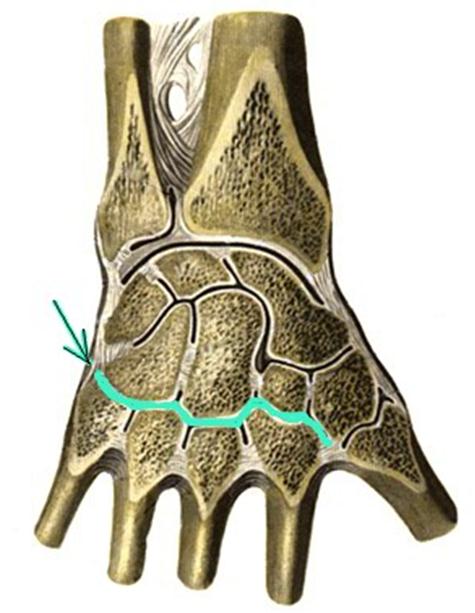

S: Стрелка указывает на art....

+:carpometacarpea

-:radiocarpea

-:mediacarpea

-:carpometocarpea policis

-:intercarpea